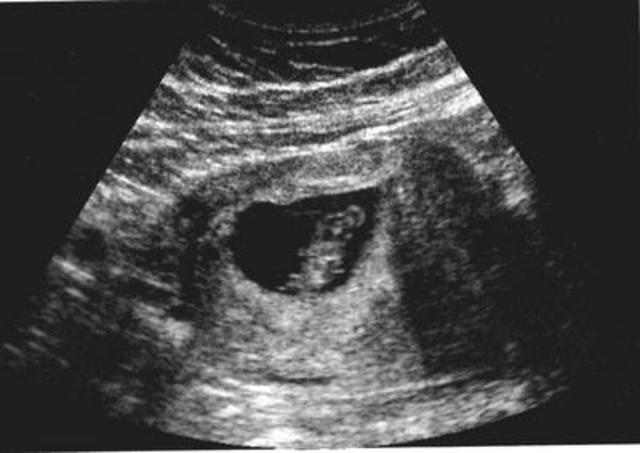

• l'échographie

l'échographie

L'échographie utilise des ultrasons qui se répercute sur le sujet à analyser et sont ensuite convertis en impulsions électriques numérisées et affichées sur ordinateur.